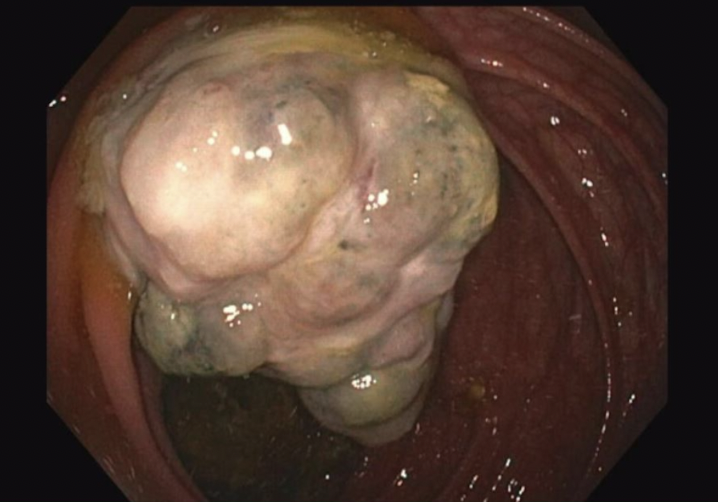

Methods/Interventions: Case 1: A 65-year-old male with a history of right nephrectomy for ccRCC eight years prior presented with intractable hiccups, a 10-lb weight loss, and profound anemia (Hgb 4.2 g/dL). CT imaging revealed a large intussuscepted mass at the splenic flexure. Colonoscopy identified a nearly fully obstructive and 6.5cm hemorrhagic fungating lesion with smooth surface and blue hue (fig 1). Biopsy was inconclusive due to necrosis. Surgical resection of a 14 cm segment of colon confirmed metastatic ccRCC with submucosal and muscularis propria invasion. All 20 lymph nodes were negative for malignancy.

Case 2: A 73-year-old female, 13 years post-nephrectomy for ccRCC, was asymptomatic but had significant anemia and a positive Cologuard test. CT imaging was unremarkable. Colonoscopy revealed a 5.2 cm fungating mass at the ileocecal valve with smooth surface and blue hue (fig.2). Biopsy was again nondiagnostic, but surgical resection revealed a metastatic ccRCC lesion. Immunostaining was positive for PAX8, RCC1, and CAIX. No lymphatic or pericolonic invasion was observed, all 24 lymph nodes were benign.

Results/Outcomes: Grossly, both masses were large, fungating and polypoid in nature, with smooth surface and blue hue, appearing different from colonic adenocarcinoma. Both patients had profound anemia despite different presenting clinical symptoms. Histologic features and immunostaining confirmed ccRCC origin in both cases. Both patients underwent successful resections with primary anastomosis and had uncomplicated recoveries. In both patients, surgical management not only provided symptomatic relief but also allowed for definitive diagnosis and staging. The absence of lymph node metastasis and the isolated nature of both lesions is a favorable prognostic factor, and resection may offer survival benefits in select patients.

Conclusion/Discussion: Colonic metastasis from ccRCC is rarely reported and can occur years after nephrectomy. Presentations vary from nonspecific symptoms like anemia, or uniquely even hiccups. Biopsies may be nondiagnostic due to tumor necrosis, but a high index of suspicion should exist with a fungating, smooth, blue hued tumor in a patient with a history of ccRCC regardless of the time since ccRCC treatment. Recognizing these rare presentations prevents misdiagnosis and delays in treatment. Surgical resection remains the standard for symptomatic or solitary lesions and may offer survival benefit in selected patients.

Figure 1: Colonoscopy image

6.5cm hemorrhagic fungating lesion with smooth surface and blue hue

6.5cm hemorrhagic fungating lesion with smooth surface and blue hue

Figure 2: Colonoscopy image

5.2 cm fungating mass at the ileocecal valve with smooth surface and blue hue

5.2 cm fungating mass at the ileocecal valve with smooth surface and blue hue